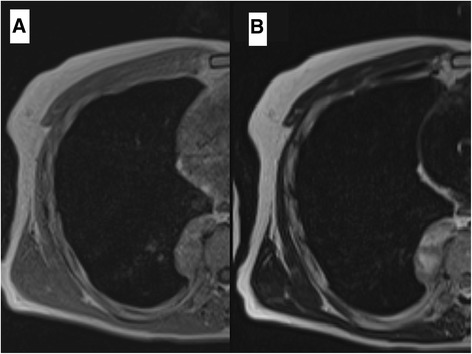

Fig. 2.

Chest MRI revealed that the signal intensity of the tumor was low in the muscles in the T1 weighted image (a) and disproportionately high in the T2 weighted image (b). The tumor invaded neither the intervertebral foramen nor the vertebral body